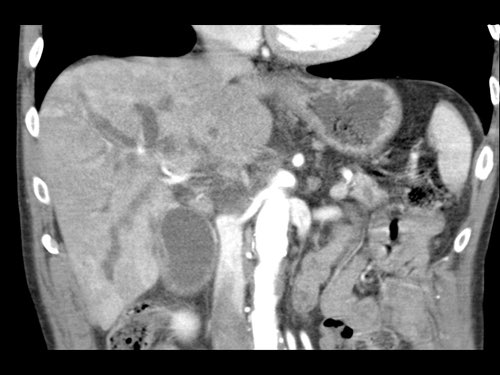

Việc sử dụng tái tạo đa mặt phẳng (multiplanar reformation) giúp cải thiện hiệu quả chẩn đoán tổng thể của CT, như được minh họa trong trường hợp này.

Tái tạo mặt phẳng coronal cho thấy một khối u nhỏ ở đầu tụy (đầu mũi tên) gây tắc nghẽn ống mật chủ.

Có vẻ chỉ có tiếp xúc hạn chế với tĩnh mạch cửa (mũi tên).

Tiếp tục xem các hình ảnh tiếp theo.

Tái tạo đa mặt phẳng vuông góc với tĩnh mạch cửa cho thấy mức độ tiếp xúc với tĩnh mạch cửa rộng hơn, từ 90 đến 180 độ (mũi tên).

Khi không có bất thường bờ viền, trường hợp này được phân loại là có thể cắt bỏ giới hạn (borderline resectable) theo tiêu chí DPCG, nhưng có thể cắt bỏ (resectable) theo tiêu chí NCCN.

Phẫu thuật cắt bỏ không kèm tái tạo tĩnh mạch cho kết quả R1, tức là có xâm lấn vi thể của khối u tại diện cắt.